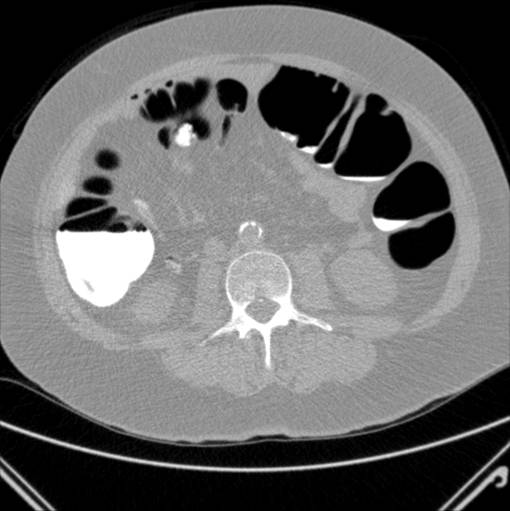

Samme patient som billedet lige før. I denne omgang er patienten skannet på maven. Igen et ud af mange billeder.